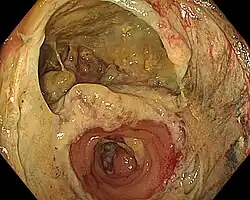

A surgical anastomosis is a surgical technique used to make a new connection between two body structures that carry fluid, such as blood vessels or bowel. For example, an arterial anastomosis is used in vascular bypass and a colonic anastomosis is used to restore colonic continuity after the resection of colon cancer.

A surgical anastomosis can be created using suture sewn by hand, mechanical staplers, or biological glues, depending on the circumstances. While an anastomosis may be end-to-end, equally it could be performed side-to-side or end-to-side depending on the circumstances of the required reconstruction or bypass. The term reanastomosis is also used to describe a surgical reconnection usually reversing a prior surgery to disconnect an anatomical anastomosis, e.g. tubal reversal after tubal ligation.

- Gastrointestinal (GI) tract: Esophagus, stomach, small bowel, large bowel, rectum, bile ducts, and pancreas. Virtually all elective resections of gastrointestinal organs are followed by anastomoses to restore continuity; pancreaticoduodenectomy is considered a massive operation, in part, because it requires three separate anastomoses (stomach, biliary tract and pancreas to small bowel). Bypass operations on the GI tract, once rarely performed, are the cornerstone of bariatric surgery. The widespread use of mechanical suturing devices (linear and circular staplers) changed the face of gastrointestinal surgery. A suture-free method for anastomosis of the colon to colon or rectum has been developed.[1][2]